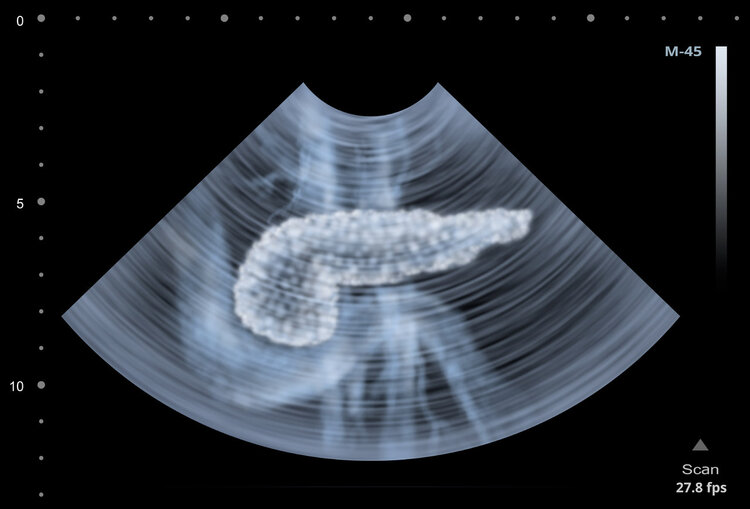

图源:南医三院

腹部CT检查提示胰腺出现明显水肿,有广泛炎性渗出;甘油三酯高达74.93mmol/L(正常值的44倍),脂肪酶1522U/ml,确诊为 急性高脂性胰腺炎 。